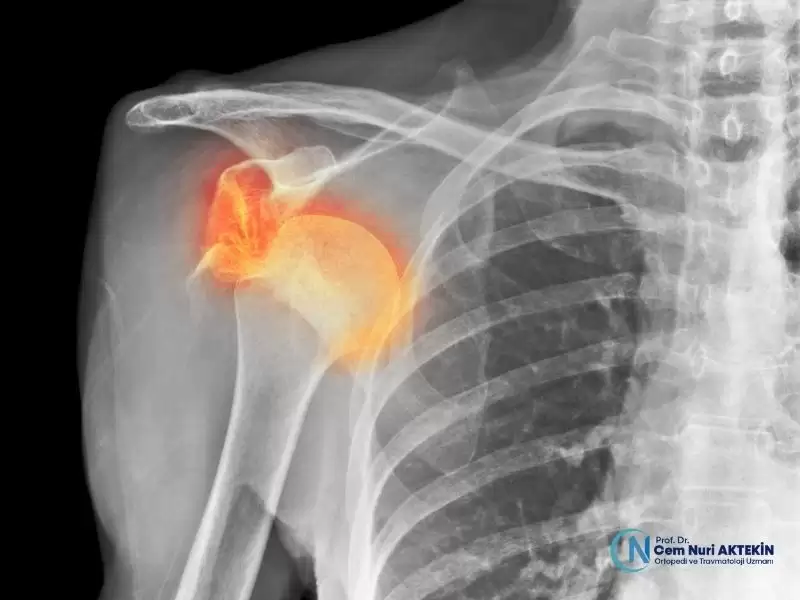

• Eklem Cerrahisi

• Spor Yaralanmaları ve Artroskopi